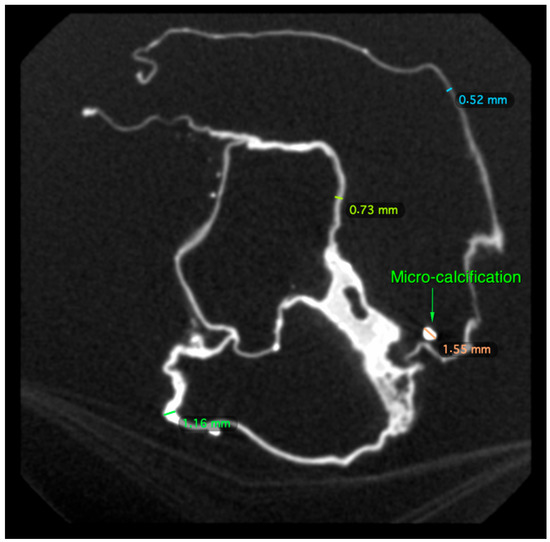

2.2. Micro-CT Scan

4.2. Micro-CT Scan